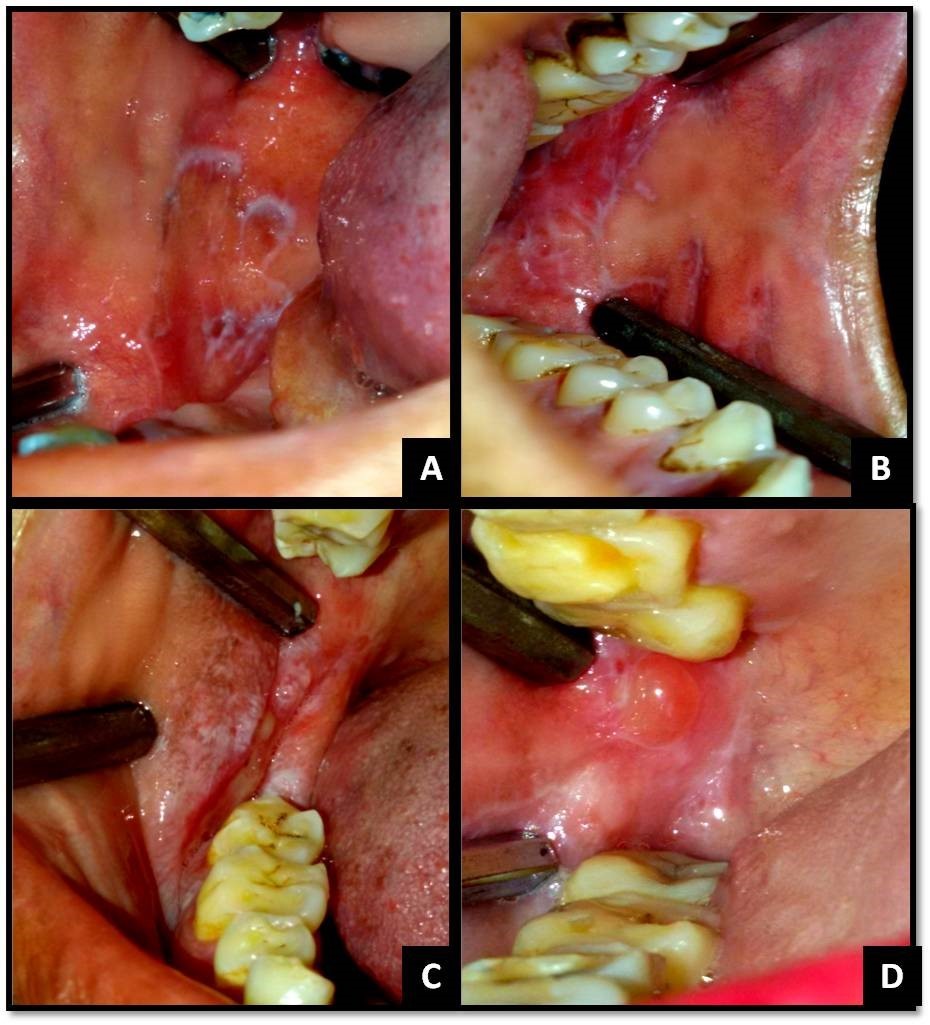

The clinical diagnostic criteria for oral lesions used in this study was- 1. The presence of keratotic, pinhead-sized, white, slightly elevated papules (papular lichen planus), which may be discrete or arranged in reticular (reticular lichen planus) or plaque-like (plaque-like lichen planus) configurations. 2. Atrophic lichen planus, characterized by thinning of the epithelium leading to the appearance of atrophic red areas within the white lesions. 3. Erosive (ulcerative) lichen planus, characterized by areas of well-defined ulceration within the above mentioned lesions. 4. Bullous lichen planus, characterized by the presence or development of bullous areas within the above mentioned lesions.1,2Representative images of OLP are shown in Figure 1 and Figure 2.

Figure 1.(A) Reticular OLP on right buccal mucosa; (B) Reticular OLP on left buccal mucosa; (C) Erosive and papular OLP on right buccal mucosa and vestibule; (D) Bullous OLP on right buccal mucosa;